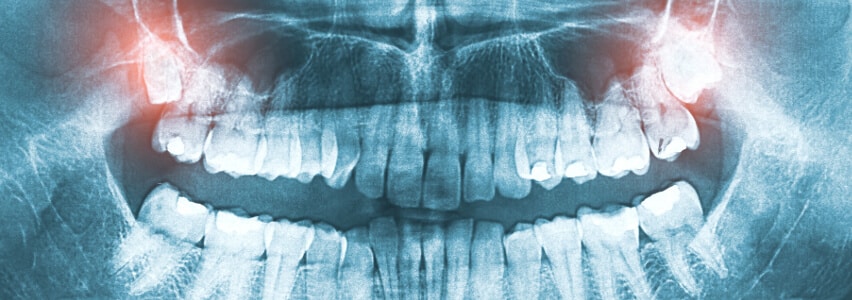

Bei der Weisheitszahnentfernung ist eine gründliche Voruntersuchung von entscheidender Bedeutung. Durch eine umfassende Voruntersuchung und die Verwendung eines dreidimensionalen DVT-Röntgenbildes kann der Zahnarzt oder Oralchirurg die genaue Lage der Weisheitszähne präzise bestimmen und den Eingriff planen. Dies minimiert das Risiko einer Verletzung des sensiblen Unterkiefernervs und verringert die Gefahr einer vorübergehenden Taubheit der Unterlippe. Während des Eingriffs erfolgt in den meisten Fällen ein Schleimhautschnitt, gefolgt von der Freilegung der Zahnkrone, der möglichen Teilung des Zahns und der Entnahme der einzelnen Zahnteile. Abschließend wird die Wunde mit Nähten verschlossen.

Fälle, in denen Menschen von nachwachsenden Weisheitszähnen berichten, sind in der Regel auf bei den Röntgenaufnahmen „übersehene“ Weisheitszähne, Hyperdontie (d.h. es sind mehr als vier Weisheitszähne im Kiefer angelegt) oder im Kiefer verbliebene Wurzelstücke, die mit den Jahren an die Oberfläche wandern, zurückzuführen.

Wenn Sie also das Gefühl haben, dass ein entfernter Weisheitszahn „nachwächst“, sollten Sie die Situation umgehend mit Ihrem Zahnarzt oder Kieferchirurgen besprechen und eine erneute Röntgendiagnostik in Betracht ziehen.